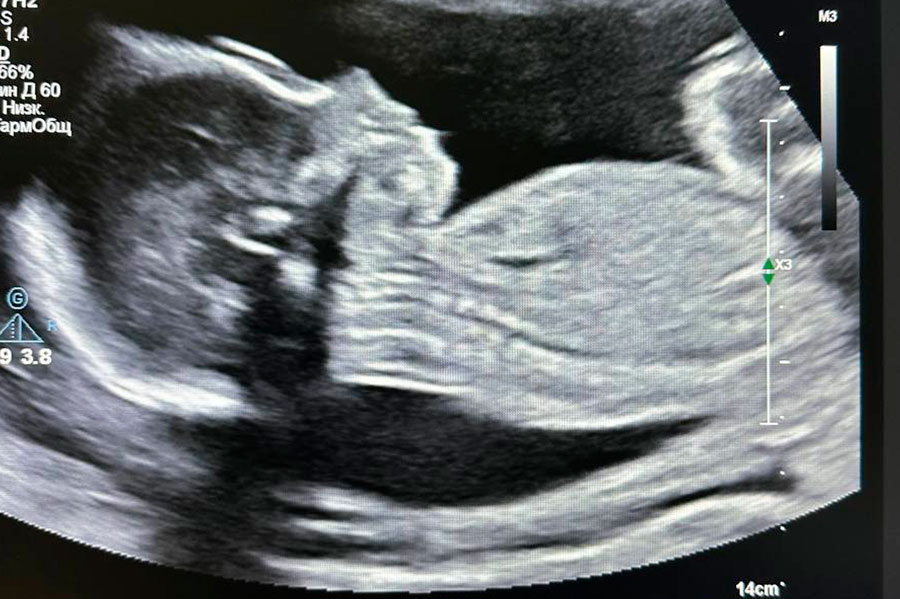

Врачам удалось не только успешно провести сложнейшее вмешательство, но и сохранить беременность. Женщина доносила ребенка до 38 недель и 2 октября родила мальчика весом 3230 г путем планового кесарева сечения. Новорожденный имеет удовлетворительные показатели по шкале Апгар.